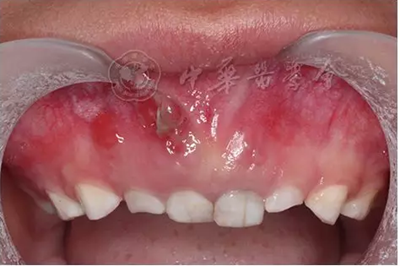

(1)疾病定義及口腔表現(xiàn):成骨不全是一種少見的先天性骨骼發(fā)育障礙性疾病,是由于Ⅰ型膠原ɑ1鏈編碼基因COL1A1和ɑ2鏈編碼基因COL1A2突變導致的結締組織遺傳性疾病,遺傳方式為常染色體顯性或隱性遺傳。成骨不全的臨床主要特征為多發(fā)性骨折、關節(jié)松弛、藍鞏膜、牙本質發(fā)育不全和進行性耳聾。根據(jù)疾病的臨床表現(xiàn)和遺傳方式分為4型,其中Ⅰ型和Ⅳ型有牙齒的表現(xiàn)?;純喝檠篮秃阊莱淑晟蛩{灰色半透明狀,釉質正?;虬l(fā)育不全、易剝脫,牙齒磨耗明顯(圖4)。患者全口牙齒磨損嚴重,面下1/3垂直距離降低。影像學檢查顯示牙齒冠根交界處變窄,早期牙髓腔寬大,隨著牙齒的不斷磨耗,大量繼發(fā)性牙本質沉積,髓腔明顯縮小甚至閉鎖,根管呈細線狀,嚴重時完全消失。組織病理學檢查可見釉質牙本質界變平,缺少正常貝殼狀結構。牙本質結構異常,牙本質小管數(shù)目減少、排列紊亂。

圖4 5歲成骨不全癥患兒乳牙呈琥鉑色,重度磨耗